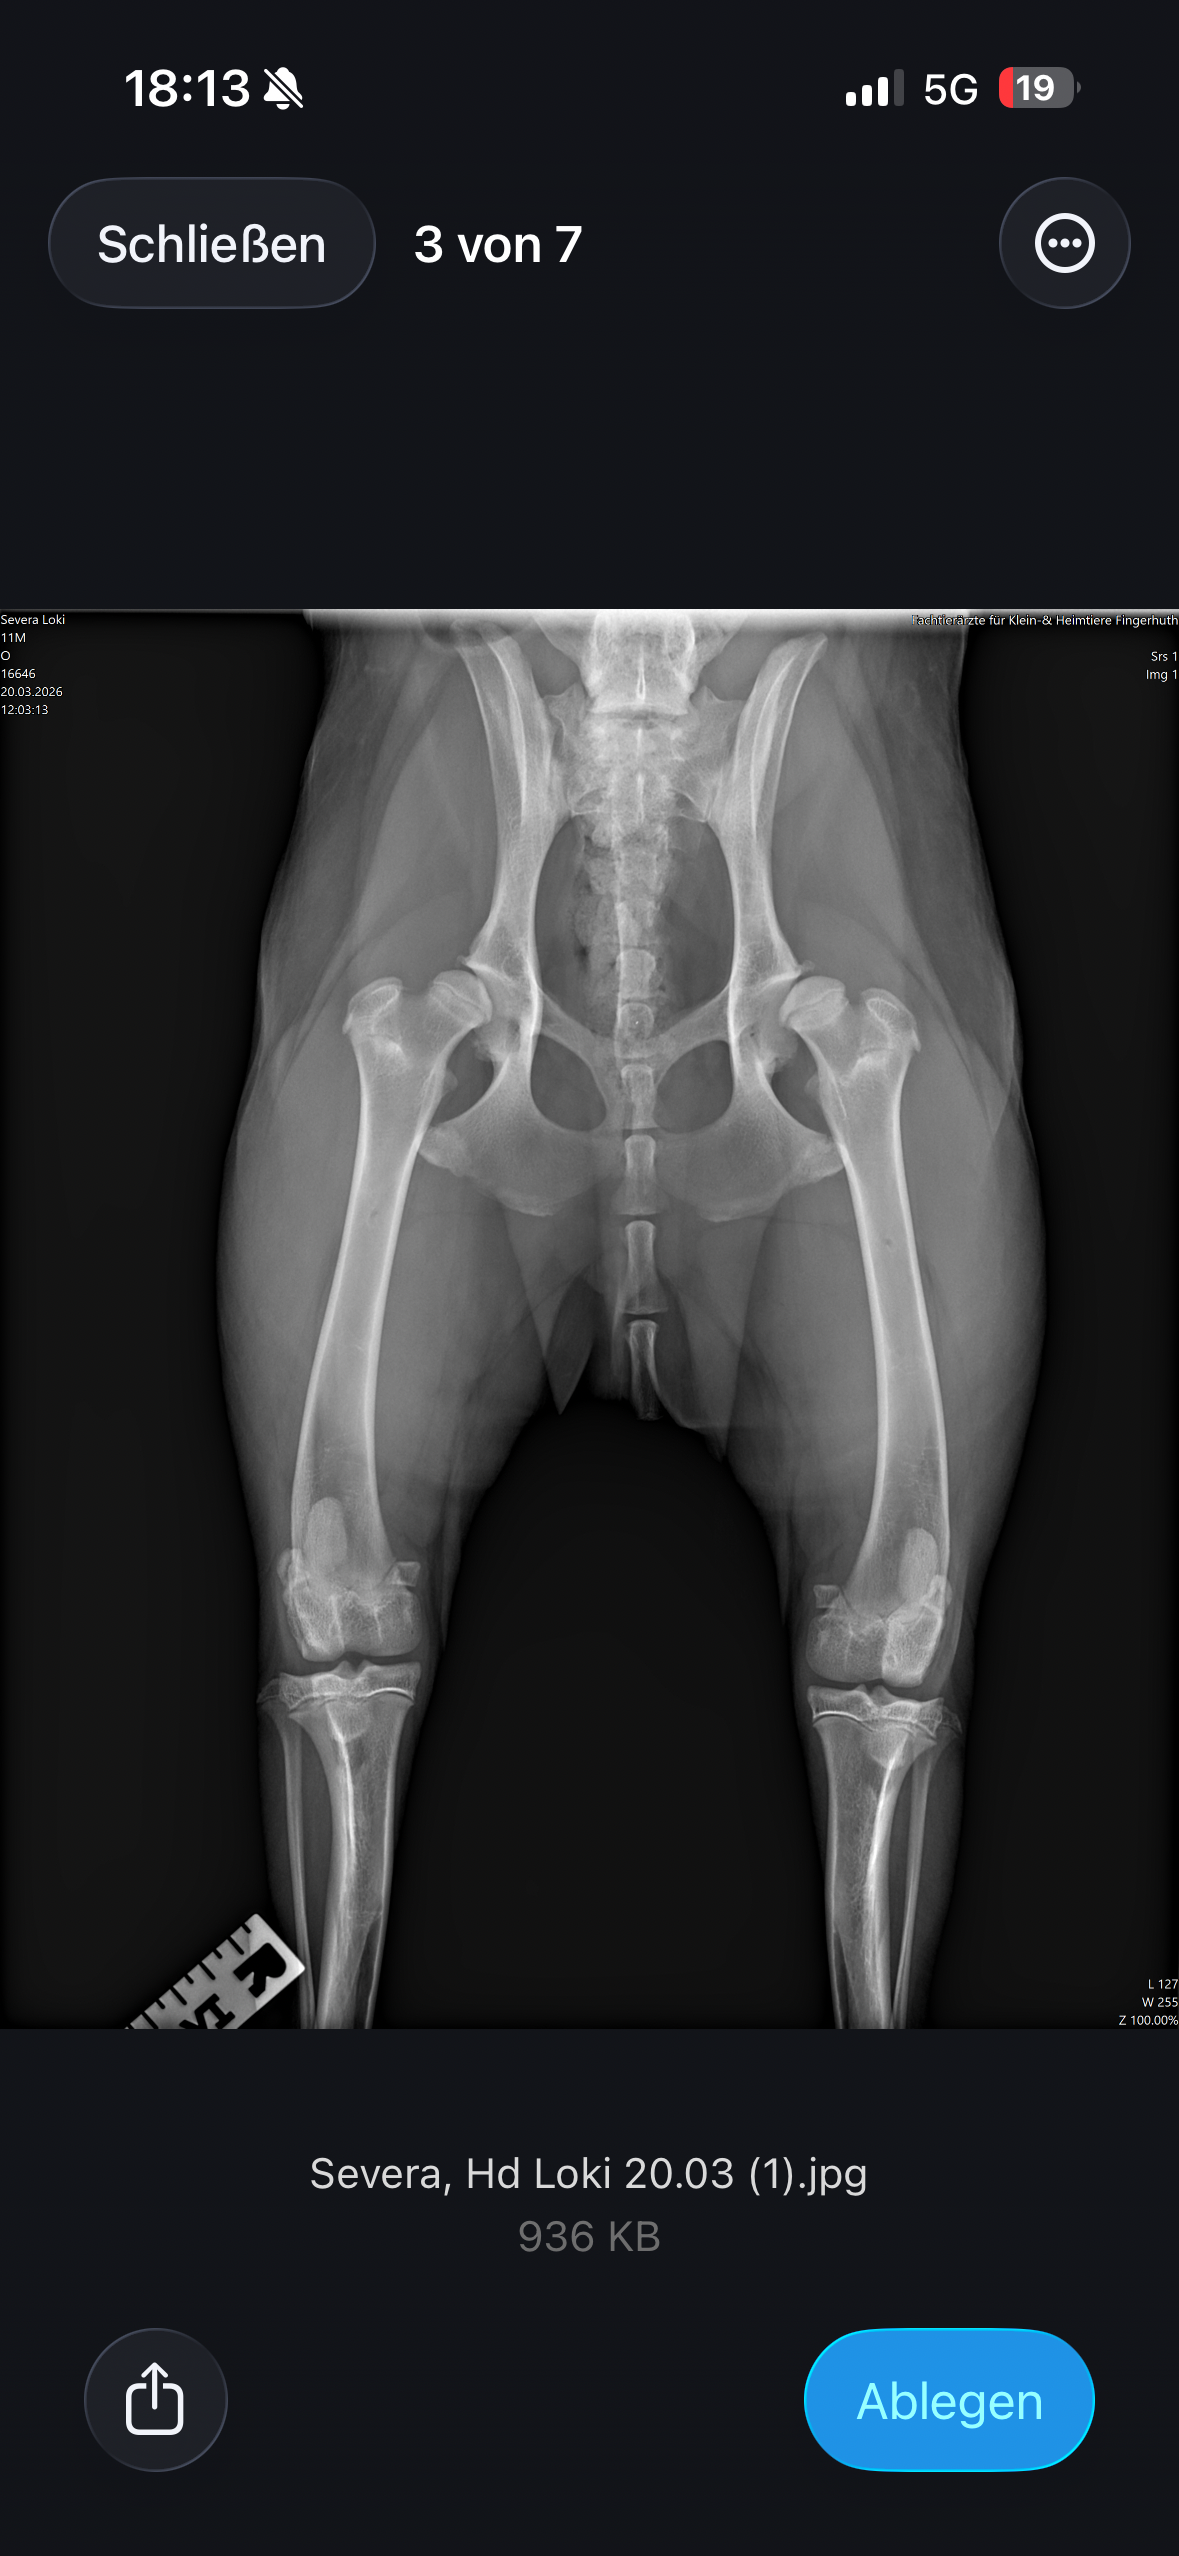

Loki leidet an Ellenbogendysplasie und Hüftdysplasie, jeweils auf beiden Seiten, was mehrere große und schwere Operationen erfordert, um ihm ein „so gut es geht“ schmerzfreies Leben zu ermöglichen. Die Gesamtkosten für die erforderlichen Behandlungen belaufen sich auf etwa 20.000 €, zu denen zusätzlich Behandlungskosten von mindestens 10.000 € für Physiotherapie, Medikamentengabe und weitere Maßnahmen kommen.

Röntgen, CT, Blutuntersuchung,mind. 3 große OP’s, Künstliche Hüftgelenke beidseits, Schmerzmittel, Physio, Wasserlaufband